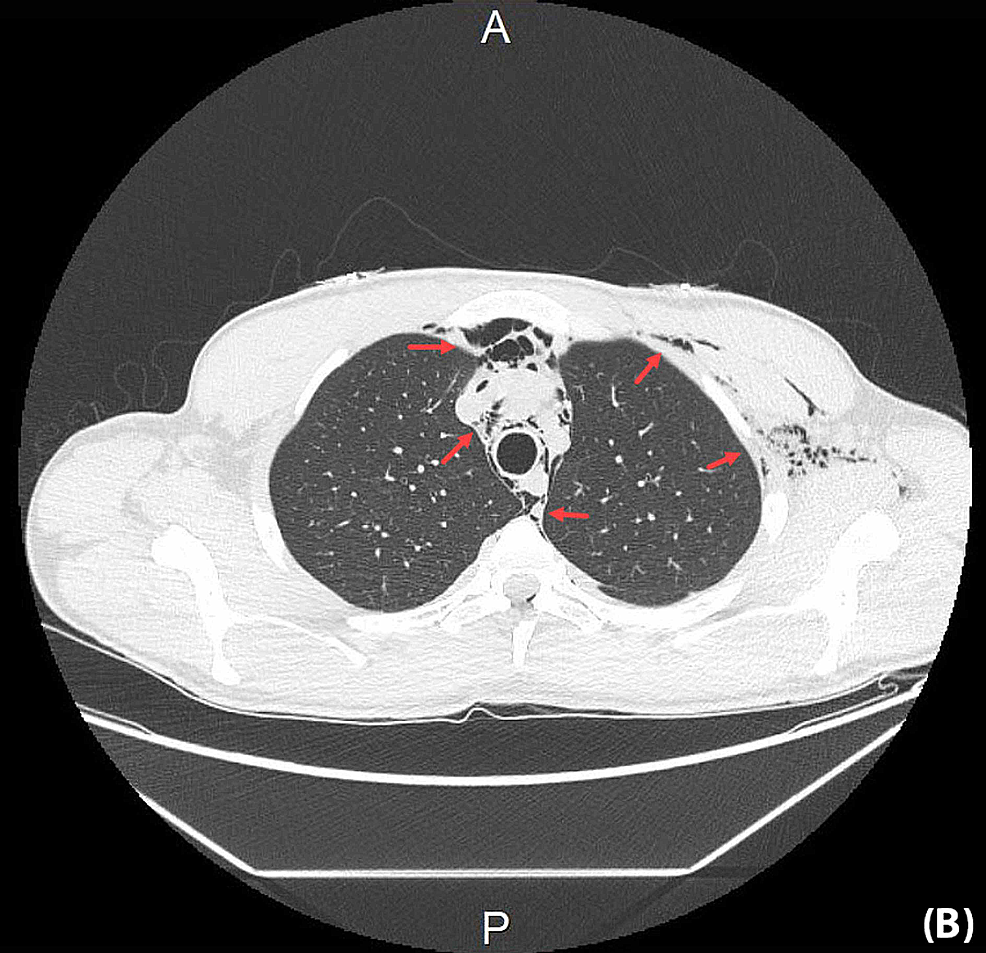

Chest CT showing the presence of interstitial air surrounding the Youngest Emphysema Case Cases had moderate airflow limitation (fev1 71.3±20.8%) but were often symptomatic, used healthcare resources frequently, had air trapping (residual volume 150.6±55.5% ref.), had reduced. Emphysema can cause chest tightness, shortness of breath, and fatigue. Using cox proportional model, we determined the comorbidities associated with mortality risk and generated comorbidomes for. Emphysema is a type of. Youngest Emphysema Case.

(PDF) Young convalescent COVID‐19 pneumonia with extensive Youngest Emphysema Case Emphysema can cause chest tightness, shortness of breath, and fatigue. Cases had moderate airflow limitation (fev1 71.3±20.8%) but were often symptomatic, used healthcare resources frequently, had air trapping (residual volume 150.6±55.5% ref.), had reduced. Using cox proportional model, we determined the comorbidities associated with mortality risk and generated comorbidomes for. Emphysema is a type of. Youngest Emphysema Case.

Young convalescent COVID‐19 pneumonia with extensive pneumomediastinum Youngest Emphysema Case Emphysema is a type of. Emphysema can cause chest tightness, shortness of breath, and fatigue. Using cox proportional model, we determined the comorbidities associated with mortality risk and generated comorbidomes for. Cases had moderate airflow limitation (fev1 71.3±20.8%) but were often symptomatic, used healthcare resources frequently, had air trapping (residual volume 150.6±55.5% ref.), had reduced. Youngest Emphysema Case.